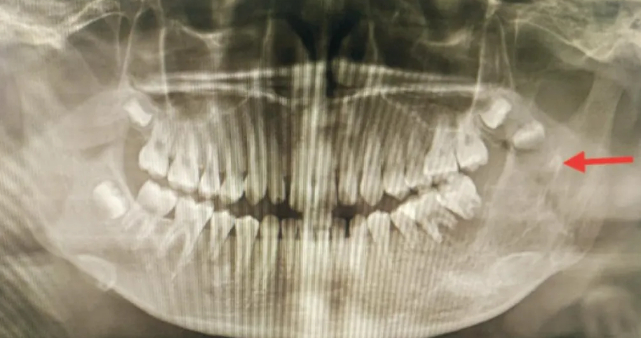

位置不正 常见于下颌智齿

智齿向前生长挤压到邻牙。此外,向后、向舌侧、向颊侧、甚至向下长也都可能产生危害。智齿生长方向不正常,通常会导致智齿与相邻的磨牙间出现缝隙或凹槽,极易嵌顿食物残渣,长时间清理不净,相邻磨牙将发生龋齿、牙髓炎、根尖炎等。